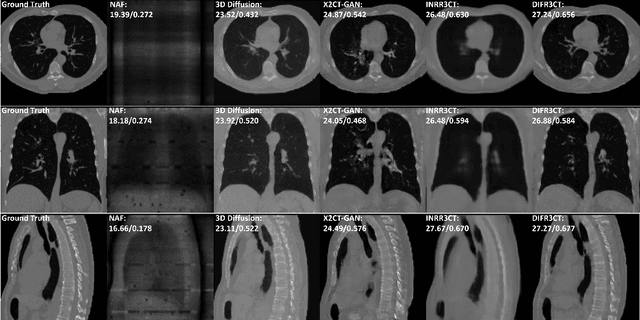

Abstract:Computed Tomography (CT) scans are the standard-of-care for the visualization and diagnosis of many clinical ailments, and are needed for the treatment planning of external beam radiotherapy. Unfortunately, the availability of CT scanners in low- and mid-resource settings is highly variable. Planar x-ray radiography units, in comparison, are far more prevalent, but can only provide limited 2D observations of the 3D anatomy. In this work we propose DIFR3CT, a 3D latent diffusion model, that can generate a distribution of plausible CT volumes from one or few (<10) planar x-ray observations. DIFR3CT works by fusing 2D features from each x-ray into a joint 3D space, and performing diffusion conditioned on these fused features in a low-dimensional latent space. We conduct extensive experiments demonstrating that DIFR3CT is better than recent sparse CT reconstruction baselines in terms of standard pixel-level (PSNR, SSIM) on both the public LIDC and in-house post-mastectomy CT datasets. We also show that DIFR3CT supports uncertainty quantification via Monte Carlo sampling, which provides an opportunity to measure reconstruction reliability. Finally, we perform a preliminary pilot study evaluating DIFR3CT for automated breast radiotherapy contouring and planning -- and demonstrate promising feasibility. Our code is available at https://github.com/yransun/DIFR3CT.